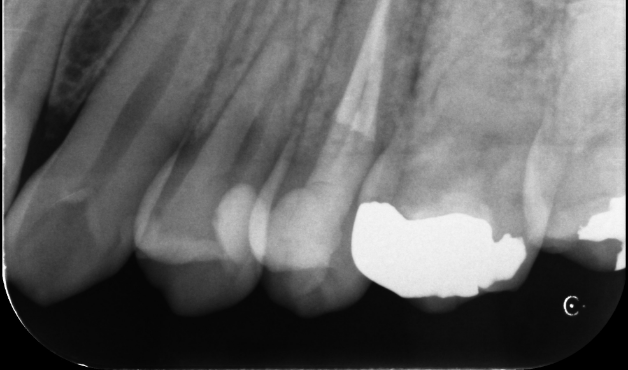

再根管治療で奥歯を残した症例

タップで写真の拡大ができます。

Before

After

主訴

噛むと違和感がある。

治療内容

リトリートメント(再根管治療・大臼歯)

ファイバーポストコア

治療期間

1ヶ月

治療費用

198,000

治療の

リスク

根尖部透過像が完全に消失しない可能性があります。